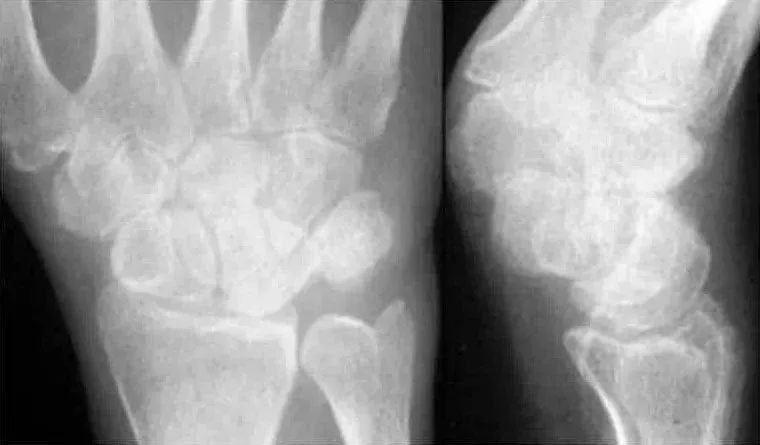

月骨脱位月骨周围脱位,苹果歪了,香蕉还在

Case 分析

1.月骨-三角骨间隙不平行,存在重叠。

2.钩状骨和月骨也存在重叠。

3.桡骨、月骨、舟骨近极和头状骨近极平行关系存在。

4.三角骨、钩骨、头状骨远极、大多角骨和舟骨远极平行关系也存在。

5.头状骨和舟骨骨折。

诊断:经舟骨、经头状骨月骨周围骨折-脱位。